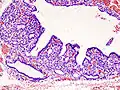

Hyperthyroidism is one of the most common endocrine conditions affecting older domesticated housecats. In the United States, up to 10% of cats over ten years old have hyperthyroidism.[60] The disease has become significantly more common since the first reports of feline hyperthyroidism in the 1970s. The most common cause of hyperthyroidism in cats is the presence of benign tumors called adenomas. 98% of cases are caused by the presence of an adenoma,[61] but the reason these cats develop such tumors continues to be studied.